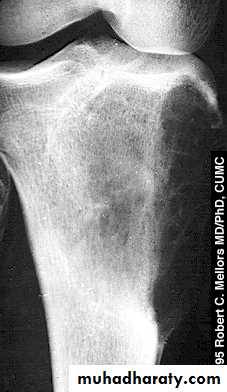

Seen in children and may disappear spontaneously with time during growth.X-ray shows eccentrically located lucent small defect in the bone

Seen mostly in the cortex of the metaphysis of long bones.Rarely if large may cause pathological fracture.